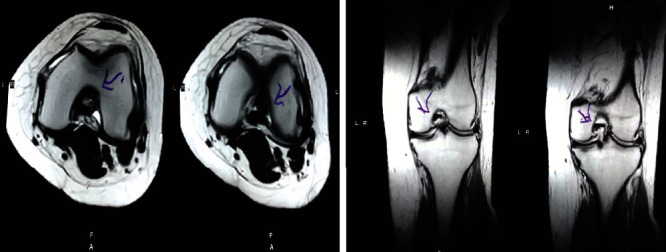

治療后一個(gè)月進(jìn)行隨訪(fǎng)。在第一次細胞治療后,患者的疼痛明顯減輕。第二次療程后,她沒(méi)有疼痛,并注意到運動(dòng)范圍有所改善。持續的物理治療也觀(guān)察到下肢肌肉力量的增加。從治療開(kāi)始(11個(gè)月前)到最后一次隨訪(fǎng)(4個(gè)月前),患者按照建議的飲食和基于運動(dòng)的方案減重了11公斤。因此,她現在整體身體健康,能夠更舒適地進(jìn)行日常生活活動(dòng)。表3顯示治療前后的MRI檢查結果。人物的圖1和的和圖2顯示半月板撕裂的治療前和治療后(1年后)圖片。觀(guān)察到損傷程度的改善圖2。

圖1:治療前MRI顯示內側和外側半月板后角的III級撕裂。

圖2:治療后MRI顯示內側和外側半月板后角的撕裂有所改善?;颊呓?jīng)歷了癥狀改善以及進(jìn)行日常生活活動(dòng)的能力增強。